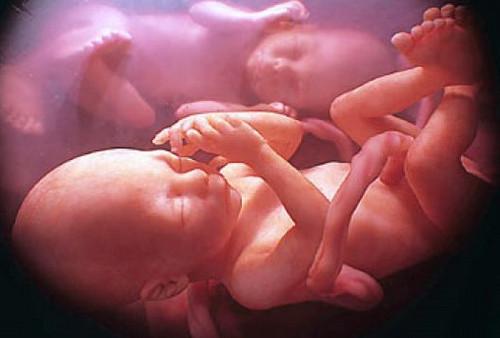

L’interazione sociale comincia nel feto: il caso dei gemelli ripresi con l’ultrasonografia

I ricercatori hanno osservato i feti utilizzando un particolare tipo di tecnica medica chiamata ultrasonografia a quattro dimensioni, attraverso la quale è possibile ottenere immagini tridimensionali ricostruite in sequenza temporale.

Le analisi sulle coppie di gemelli sono avvenute alla quattordicesima e alla diciottesima settimana di gestazione e, in entrambi i periodi, i ricercatori hanno riscontrato nei fratelli, alcuni movimenti volontari e rivolti l'uno nei confronti dell'altro.

I gemelli, già a partire dalla quattordicesima settimane e con una decisa intensificazione durante la diciottesima, si cercano l’un l’altro con movimenti intenzionali e utilizzano il suddetto movimento quasi per coccolarsi.